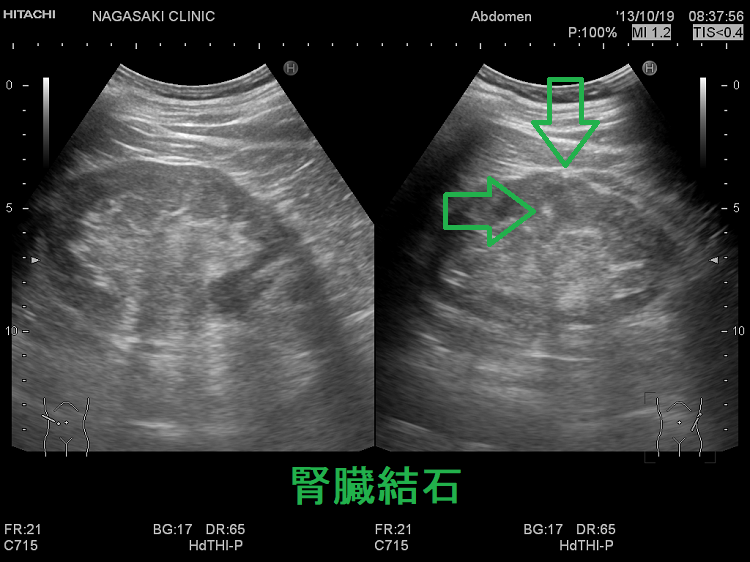

- 過剰な血清カルシウムが腎結石(腎臓結石)・尿路結石を形成し腎不全

原発性副甲状腺機能亢進症の約4%に、高カルシウム血症による腎結石(腎臓結石): 内分泌尿路結石を認めます[Urolithiasis. 2018 Oct;46(5):453-457.][J Clin Endocrinol Metab. 2011 Aug;96(8):2377-85.]。

再発性あるいは多発性(散在性)尿路結石患者の12.6%が原発性副甲状腺機能亢進症とされます(泌尿器科紀要 (1984), 30(7): 975-979)。

原発性副甲状腺機能亢進症の腎結石(腎臓結石): 内分泌尿路結石はリン酸カルシウム結石です。[JAMA Surg. 2020 Sep 1;155(9):861-868.]